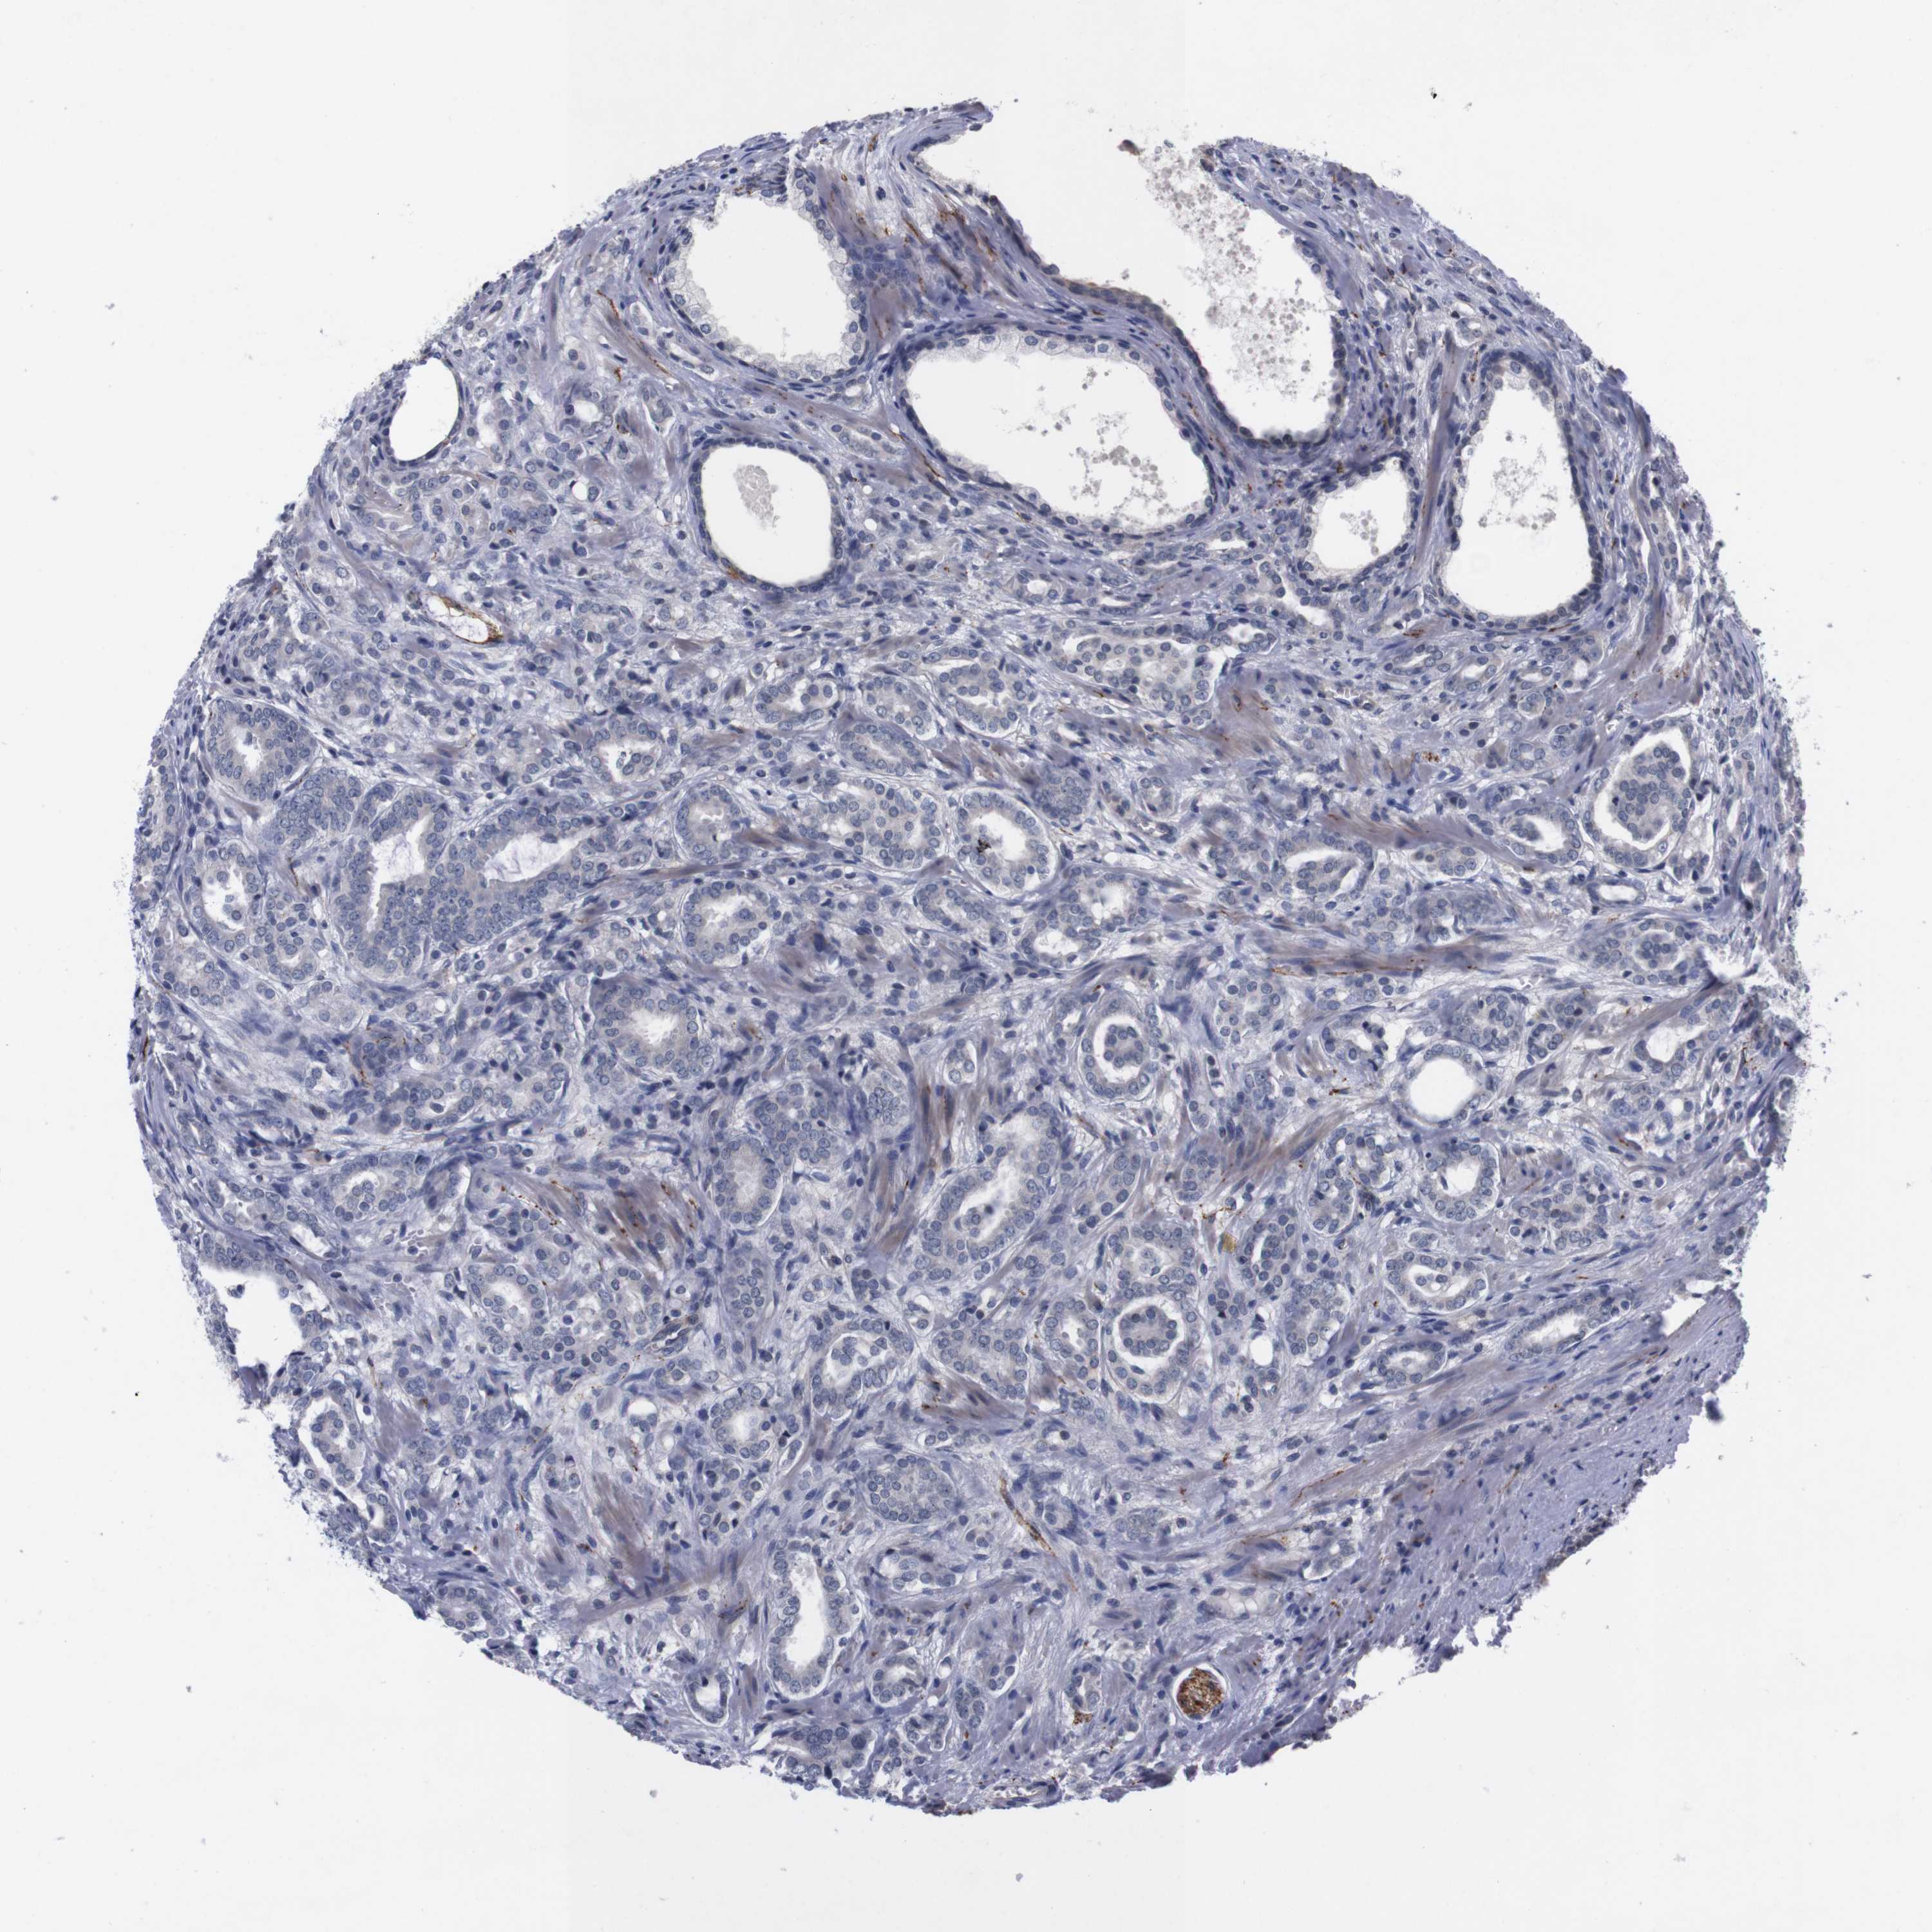

PROSTATE CANCER - Protein expressioni

A mouse-over function shows sample information and annotation data. Click on an image to view it in a full screen mode. Samples can be filtered based on level of antibody staining by selecting one or several of the following categories: high, medium, low and not detected. The assay and annotation is described here.

Note that samples used for immunohistochemistry by the Human Protein Atlas do not correspond to samples in the TCGA dataset.

Antibody stainingi

Antibody staining in the annotated cell types in the current human tissue is reported as not detected, low, medium, or high, based on conventional immunohistochemistry profiling in selected tissues. This score is based on the combination of the staining intensity and fraction of stained cells.

Each image is clickable and will lead to virtual microscopy that enables deeper exploration of all samples and also displays staining intensity scores, fraction scores and subcellular localization as well as patient and tissue information for each sample.

Antibody HPA006746

Antibody CAB009805

Staining

High

Medium

Low

Not detected

Intensity

Strong

Moderate

Weak

Negative

Quantity

>75%

75%-25%

<25%

None

Location

Nuclear

Cytoplasmic/membranous

Cytoplasmic/membranous,nuclear

Adenocarcinoma, Low grade

Adenocarcinoma, High grade